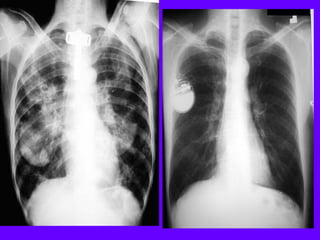

Dissecting Aneurysm

Mediastinal widening

Inlet to outlet shadow

on left side

Retrocardiac: Intact

silhouette of left heart

margin

Pulmonary artery

overlay sign: Density

behind left lower lobe

Wavy margin